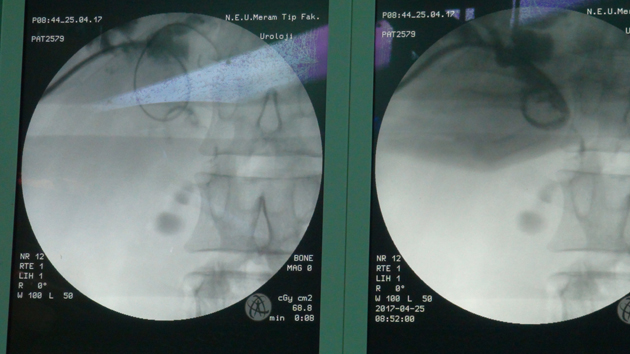

Tetkiklerde karaciğerinde 3 santimetre çapında taş olduğu tespit edilen Esen'e, müdahale için hastane doktorları harekete geçti.

Bir hastalık için tarama kanallarına girildiğinde 10 bin, 100 bin, 1 milyon yayın bulunabileceğine dikkati çeken Öztürk,"Bu şekilde bir tedavi için arama yaptığımızda 70-80 yayın karşımıza çıkıyor. Bunların içerisinde de Seyit Esen gibi vaka sayısı 2-3 yayına düşüyor. Çok az ve büyük aletlerle yapılmış. İlk olarak gerçekleştirdiğimiz ultra mini yöntem, bu tür hastaların tedavisinde umut olacak." diye konuştu.

Öztürk, karaciğer taşı, safra kesesi alınmış veya safra yolları yeniden bağırsağa bağlanmış hastalarda görülebildiğini kaydetti.